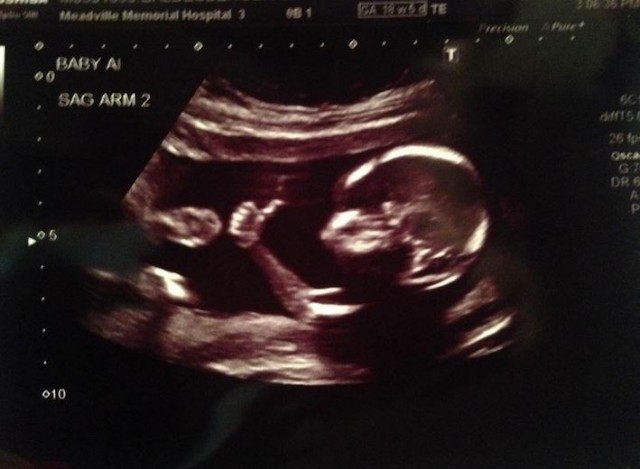

Συνήθως τα υπερηχογραφήματα όλων των εμβρύων τα βλέπουν οι υποψήφιοι γονείς, ο γιατρός και κάποιοι συγγενείς.

Υπάρχει όμως ένα έμβρυο, που το έχουν δει 2,25 εκατομμύρια φορές στο Reddit.

Όλα ξεκίνησαν όταν ο χρήστης meancloth πόσταρε στο reddit την φωτογραφία από τον υπέρηχο την γυναίκας του, στον οποίο φαίνεται το έμβρυο να έχει σηκωμένο το ένα χέρι σαν να λέιε “Όλα είναι ΟΚ”.

Μέσα σε λίγες ημέρες από τότε που ανέβασε την φωτογραφία έχει γίνει το πιο διάσημο έμβρυο στο διαδίκτυο.